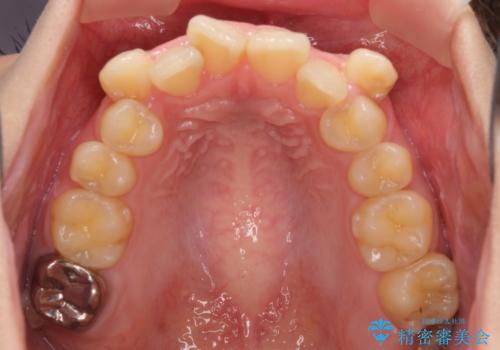

上顎の八重歯と下顎前歯の欠損 ワイヤー装置による抜歯矯正

- 上顎の八重歯を気にして来院された患者様です。

診察したところ、下顎前歯が2本欠損していたため、上下のバランスを取りながら八重歯を改善するため、上顎左右第一小臼歯2本を抜歯することとしました。

下顎左右大臼歯の歯根部に病変があったため、矯正治療前に根管治療を行い、矯正治療後にセラミッククラウンによる補綴治療を行うこととしました。